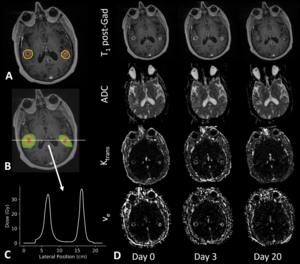

Publication: PLoS One. 2018 Nov 26;13(11):e0207933. PMID: 30475887 | PDF Authors: Winter JD, Moraes FY, Chung C, Coolens C. Institution: Radiation Medicine Program, Princess Margaret Cancer Center and University Health Network, Toronto, Ontario, Canada. Abstract: Our objective was to investigate direct voxel-wise relationship between dose and early MR biomarker changes both within and in the high-dose region surrounding brain metastases following stereotactic radiosurgery (SRS). Specifically, we examined the apparent diffusion coefficient (ADC) from diffusion-weighted imaging and the contrast transfer coefficient (Ktrans) and volume of extracellular extravascular space (ve) derived from dynamic contrast-enhanced (DCE) MRI data. We investigated 29 brain metastases in 18 patients using 3 T MRI to collect imaging data at day 0, day 3 and day 20 following SRS. The ADC maps were generated by the scanner and Ktrans and ve maps were generated using in-house software for dynamic tracer-kinetic analysis. To enable spatially-correlated voxel-wise analysis, we developed a registration pipeline to register all ADC, Ktrans and ve maps to the planning MRI scan. To interrogate longitudinal changes, we computed absolute ΔADC, ΔKtrans and Δve for day 3 and 20 post-SRS relative to day 0. We performed a Kruskall-Wallice test on each biomarker between time points and investigated dose correlations within the gross tumour volume (GTV) and surrounding high dose region > 12 Gy via Spearman's rho. Only ve exhibited significant differences between day 0 and 20 (p < 0.005) and day 3 and 20 (p < 0.05) within the GTV following SRS. Strongest dose correlations were observed for ADC within the GTV (rho = 0.17 to 0.20) and weak correlations were observed for ADC and Ktrans in the surrounding > 12 Gy region. Both ΔKtrans and Δve showed a trend with dose at day 20 within the GTV and > 12 Gy region (rho = -0.04 to -0.16). Weak dose-related decreases in Ktrans and ve within the GTV and high dose region at day 20 most likely reflect underlying vascular responses to radiation. Our study also provides a voxel-wise analysis schema for future MR biomarker studies with the goal of elucidating surrogates for radionecrosis. "To enable spatially registered voxel-wise analyses, we developed a rigorous in-house registration pipeline to perform all image registration steps as well as visualize image registration results using Python (Python Software Foundation), interacting with 3D Slicer." Funding:

|